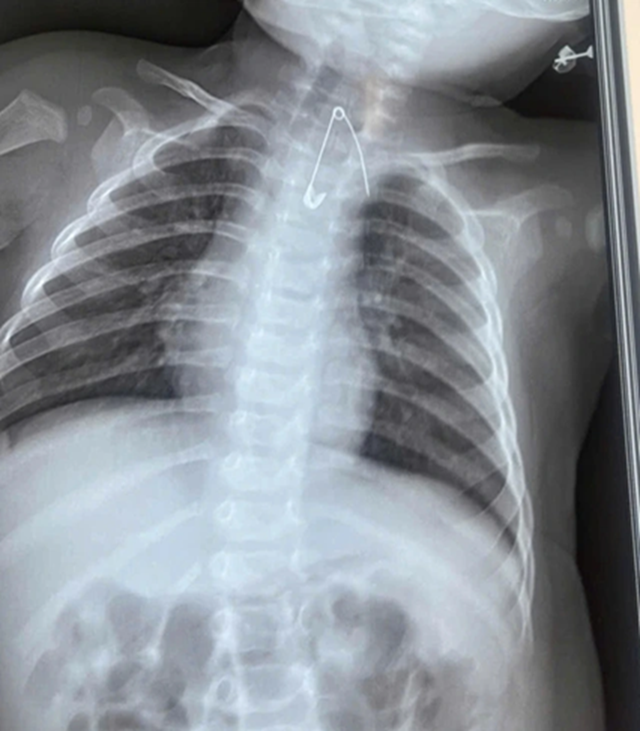

Người nhà cho biết, gia đình có thói quen dùng kim tây (kim băng) ghim bùa bình an vào áo của bé. Qua thăm khám lâm sàng và thực hiện các xét nghiệm cận lâm sàng, các bác sĩ phát hiện một dị vật là kim tây nằm trong mô mềm, ở vị trí sát động mạch chủ, rất nguy hiểm.

Bệnh nhi sau đó được ê-kíp phẫu thuật lấy thành công kim băng, ngăn ngừa các biến chứng nghiêm trọng có thể xảy ra.